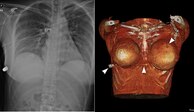

Mejores que los chalecos antibalas

Mujer recibe un disparo e implantes del pecho la salvan